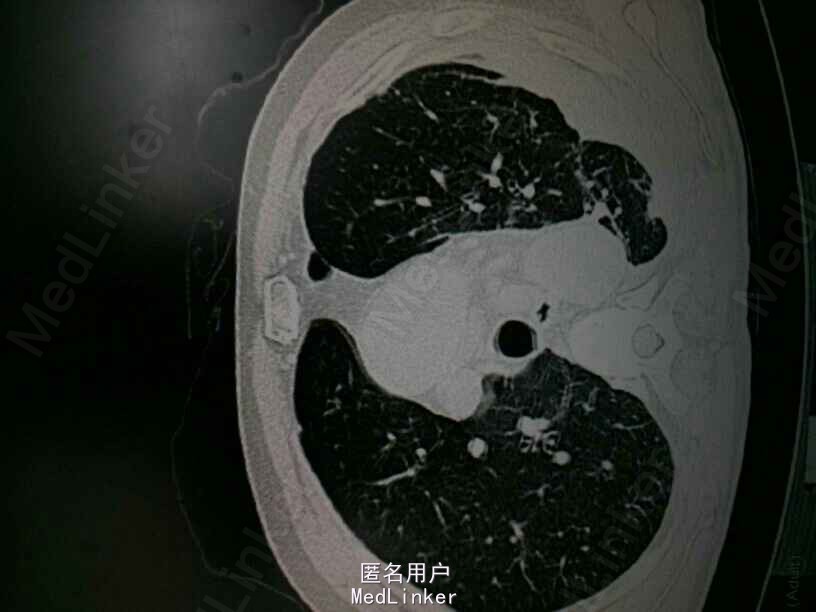

CT提示:左肺多发大小不等的囊状气腔,部分病灶壁较厚,可见液平。左肺可见斑片状渗出。左侧胸腔积液。考虑左肺多发肺大泡伴感染,左侧胸腔积液。双肺气肿。

诊断: 肺大泡 肺部感染 胸腔积液